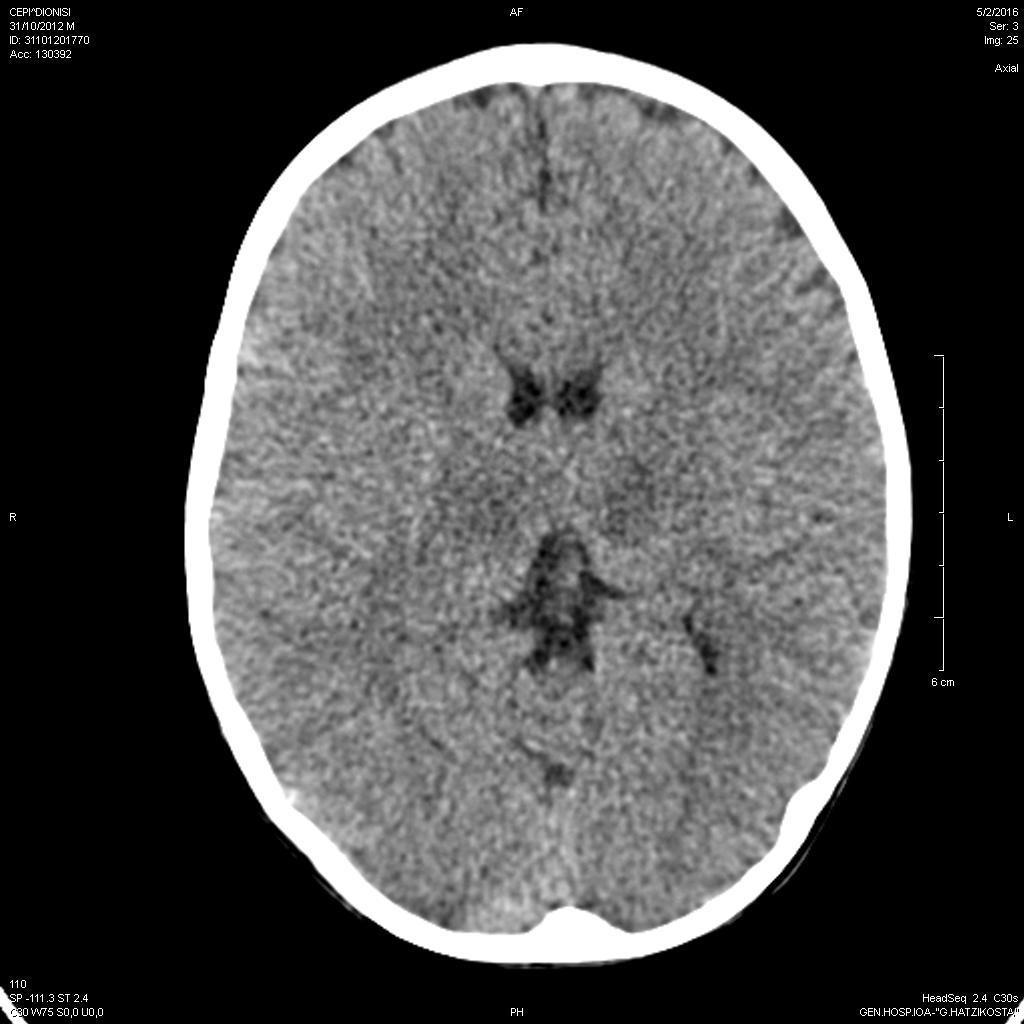

Οξεία εγκεφαλοπάθεια, ηπατική και νεφρική ανεπάρκεια από ιό γρίπης Α σε ανοσοεπαρκές νήπιο.

Μαργαρίτα-Ευθαλία Παπασάββα, Ιλιάδα Νάκου, Βασιλική Γκέτση

Acute encephalopathy, renal and hepatic failure in an immunocompetent toddler with influenza type A infection.

Margarita-Efthalia Papasavva, Iliada Nakou, Vasiliki Gketsi